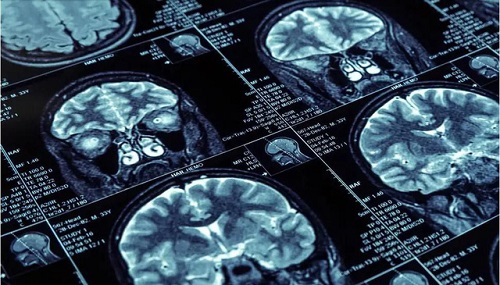

Các nhà nghiên cứu của Viện Sức khỏe Tâm thần Quốc gia cho biết, quét não từ hàng trăm người trẻ tuổi cho thấy những hiệu ứng này sẽ được ổn định trong thời thơ ấu và thanh thiếu niên.

Đối với nghiên cứu, được công bố trên Tạp chí Thần kinh học, các nhà nghiên cứu đã xem xét 1.243 lần quét MRI não từ hơn 623 người trẻ trong độ tuổi từ 5 đến 25. Trong khi điểm số kinh tế xã hội được sử dụng không tính đến thu nhập gia đình thì yếu tố quyết định chính là tình trạng kinh tế xã hội, các yếu tố nghề nghiệp và sự giáo dục của cha mẹ.

Tuy nhiên, nghiên cứu này đưa ra kết quả rõ ràng hơn nữa và cho thấy tình trạng kinh tế xã hội ở thời thơ ấu có ảnh hưởng rõ rệt đến hai khu vực của não là đồi thị và vân.

Đồi thị là một khu vực quan trọng ở trung tâm của bộ não liên quan đến việc truyền và xử lý thông tin cảm giác, và một khối đồi thị càng lớn thì đứa trẻ đó suy nghĩ càng nhanh và chỉ số IQ càng cao.

Sự khác biệt về kích thước và độ phức tạp của các vùng não này được theo dõi gắn với sự liên quan đến tình trạng kinh tế xã hội, và điều này đã được chứng minh để dự đoán kết quả cuộc sống trong tương lai.